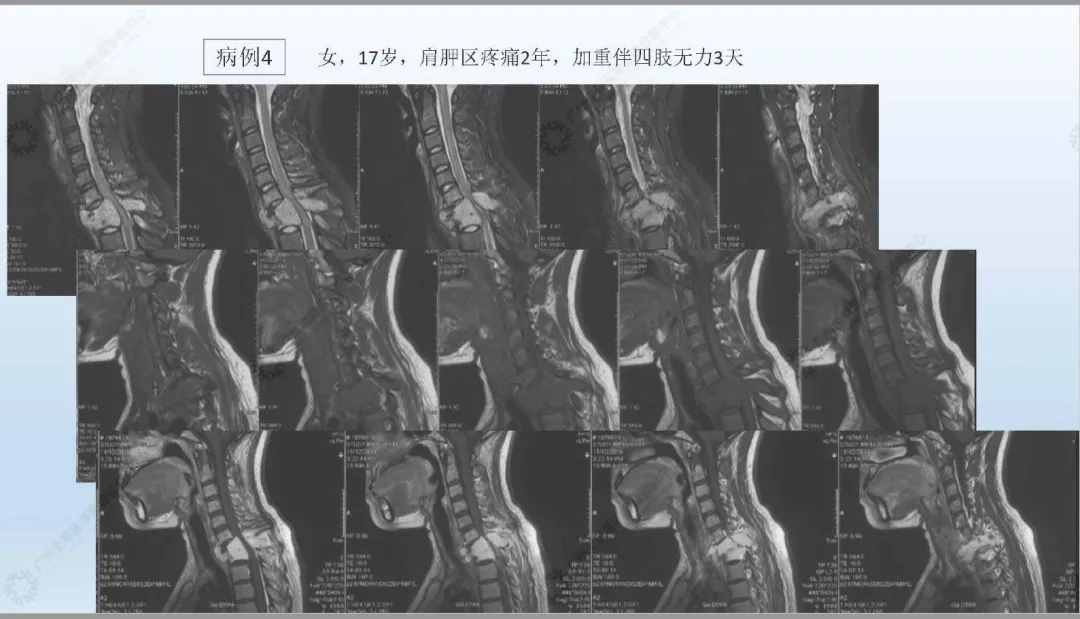

从影像检查技术的发展——什么是MRN——MRN的优势——MRN临床应用四个方向进行阐述,并引用大量案例辅助说明。